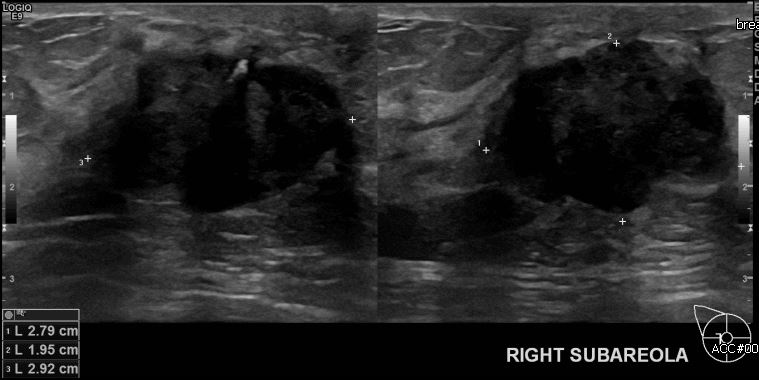

우측 유방 멍울과 유두의 함몰로 내원하신 60대 여성분으로 우측 유방 우두밑  의심스러운 멍울 조직검사 시행하여 우측 침윤성 유관암 진단 되었습니다.